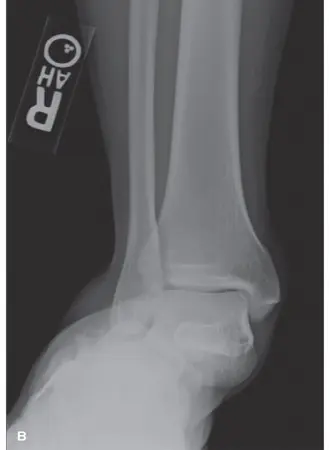

الأشعة السينية (X-rays):

- هي الخطوة الأولى دائمًا.

- يمكن أن تظهر عدم القدرة على تحقيق رد تشريحي كامل للكسر، مع بقاء تباعد بين الشظايا أو عدم استقامة المفصل.

- قد تظهر علامات غير مباشرة على وجود نسيج رخو محتجز، مثل اتساع غير مبرر في المساحة بين الشظايا.